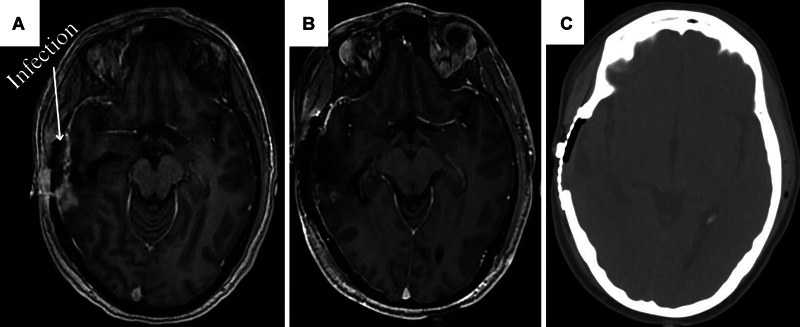

Methods: We report the case of a 37-year-old female patient with recurrent GBM and associated wound healing complications who underwent single-stage GammaTile surgically targeted radiation therapy combined with microvascular free flap scalp reconstruction.

Results: Immediate free flap reconstruction over the site of GammaTile implantation did not result in any wound healing complications and did not compromise the viability of the transplanted tissue. This approach also provided immediate and localized radiation, possibly enhancing patient progression-free survival while reducing the likelihood of radiation-induced adverse effects.

Conclusion: We report the first case of GammaTile implantation with immediate reconstruction of the overlaying soft tissue defect with a free flap. Despite the immediate local radiation produced by the tiles abutting the deep surface of the free flap, there were no complications noted in the vascularity of the transplanted tissue. This finding provides preliminary evidence supporting the safety of using free tissue transfer alongside GammaTile implantation for complex reconstruction.